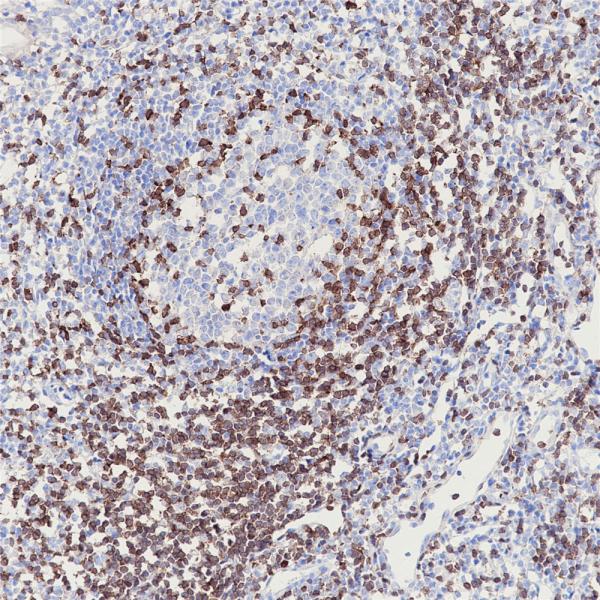

ZAP-70

BP6106